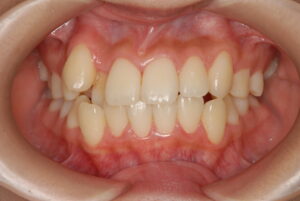

実際の症例紹介(20代女性/裏側ワイヤー矯正)

治療前

治療後

・主訴:八重歯と前歯の突出

・治療法:裏側からのワイヤー矯正(リンガル)

・治療期間:約1年半〜2年(目安)

・予想される副作用・リスク:装置装着後の違和感・疼痛、発音のしづらさ、一時的な咀嚼効率低下、ブラッシング不良によるむし歯・歯周病リスク など

※写真は代表的な症例です。口腔内の状態により治療法や期間は異なります。詳細は初診相談でご説明します。